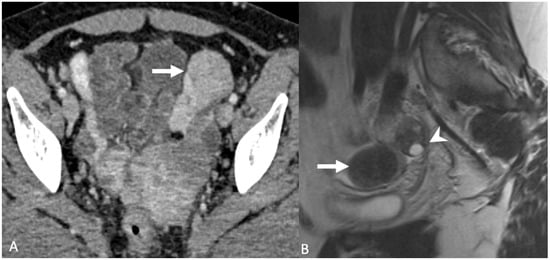

5.2.1. Uterine Vasculature

5.2.2. Leiomyoma